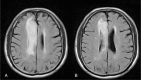

Patient concerns: The 77-year-old male with cerebral infarction in the territory of the right anterior cerebral artery only underwent conservative treatment including hydration and aspirin in the acute post-stroke stage.

Diagnosis: He was diagnosed as stroke based on the clinical presentations and imaging findings.

Intervention: Once the patient was in stable condition, he underwent a daily hour-long ILIB (He-Ne laser) for ten consecutive days during the sub-acute post-stroke stage.

Outcomes: We used single-photon emission computed tomography (SPECT) before and after intravascular laser irradiation to detect changes in cerebral and cerebellar perfusion. Then, we compared the two images. CCD was detected using the first SPECT. After intervention by ILIB, the second SPECT showed greater perfusion in the affected cerebellar hemisphere.